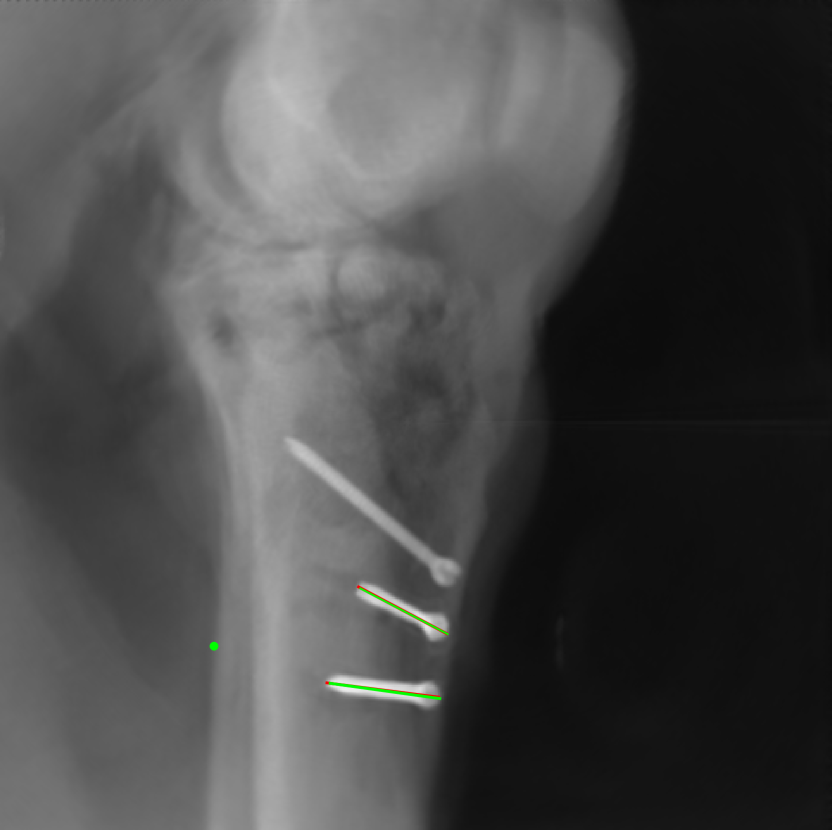

The complementary view setting for learning perspective deformation is also evaluated on real CBCT projection data. In this evaluation, real CBCT projection data from a dataset of knees with metal implants is used for testing, while DRRs created from volumetric CT datasets with inserted metals is used for training. Three exemplary DRR perspective projection images for training are displayed in Fig. 13, in which synthetic metal implants are inserted [34]. The appearance, e.g., image contrast and metal image resolution, of such DRR training images is different from that of real projection images in Fig. 14. In Fig. 14, the results for three knees, with and without metal implants, are displayed. The first and second rows are the 0superscript00^{\circ} and 180superscript180180^{\circ} perspective projections, respectively, rebinned to the virtual detector with geometric calibration based on their respective principal points and projections of the world origin. The third row displays their difference images, where the magnitude of deviation increases from the center towards the outside like it does in DRRs with an ideal scan trajectory (e.g., Fig. 6(e)), although real projection data suffer from various physical effects like beam hardening and Poisson noise. The fourth row displays the RGB stacks of 0superscript00^{\circ} and 180superscript180180^{\circ} perspective projection images. The magenta and green regions indicate structures with considerable perspective deformation, for example, the knee patella in Fig. 5.4, the top parts of the two metals in Fig. 5.4, and the bottom two screws in Fig. 5.4. The fifth row displays reference images, which are orthogonal projections of iterative reconstruction volumes from measured CBCT projection data. In the reference images, a total of five landmarks are selected, with the positions being marked by the green dots: In Fig. 5.4, two positions at the edges of the knee patella are marked; In Fig. 14(e) and Fig. 14(f), one position at the left edge of the fibula is marked for each image. In addition, a rectangular frame for the two metals is marked by the green dashed lines, while its width and height are indicated by the green solid lines, which are 29.71 mm and 111.99 mm, respectively. In Fig. 14(f), the centerlines of the bottom two screws are sketched by the green lines, which have the lengths of 17.14 mm (middle screw) and 19.38 mm (bottom screw). The corresponding rectangular frame for the two metals and the screw centerlines in the perspective projection images are marked as well, but in red color. In Fig. 14(a), the width and height of the metals are 32.56 mm and 109.85 mm, which have deviations of 2.84 mm and -1.95 mm to the reference ones, respectively. In Fig. 14(b), the centerline lengths are 18.91 mm and 19.54 mm, which have deviations of 1.77 mm and 0.16 mm, respectively. Although the bottom screw has little length deviation to the reference, the orientations of both screws are obviously deviated. The sixth row shows the results of Pix2pixGAN using 0superscript00^{\circ} and 180superscript180180^{\circ} polar inputs. For all of the landmarks, the green reference dots are all located accurately in the Pix2pixGAN images. The rectangular reference frame also accurately covers the metals in Fig. 14(g). In Fig. 14(h), although the two red centerlines do not exactly overlap with the green one, they are very close in lengths and orientations. Please zoom in for better visualization.

In the real cadaver data, certain metal implants are distorted in Pix2pixGAN predictions. For example, the long metal rod indicated by the red arrow is no longer straight in Fig. 18(c), although its position is between the corresponding magenta and green rods in Fig. 18(b). Another limitation is that certain structures like thin K-wires from 0superscript00^{\circ} and 180superscript180180^{\circ} perspective projection images will remain as shadows in the Pix2pixGAN prediction, for example, those indicated by the blue arrows in Fig. 18(c).